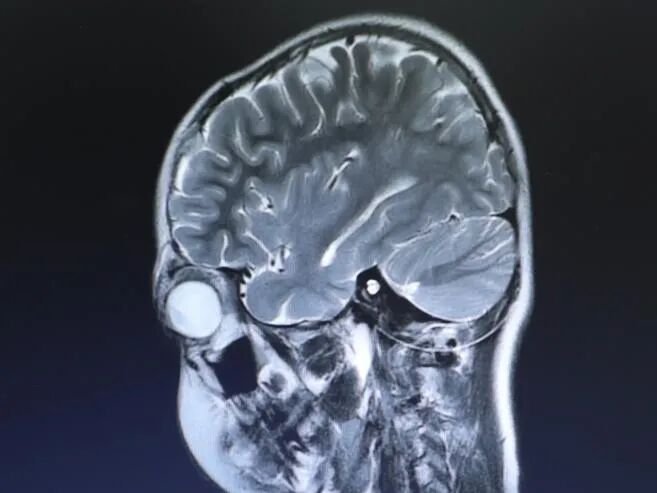

成人用户 右侧植入SYNCHRONY人工耳蜗

核磁检查原因:耳蜗术后进行垂体瘤检查

从影片看患者的垂体瘤近期有出血和生长的情况,目前需要进一步完成其它相关检查,再评估是否需要手术。